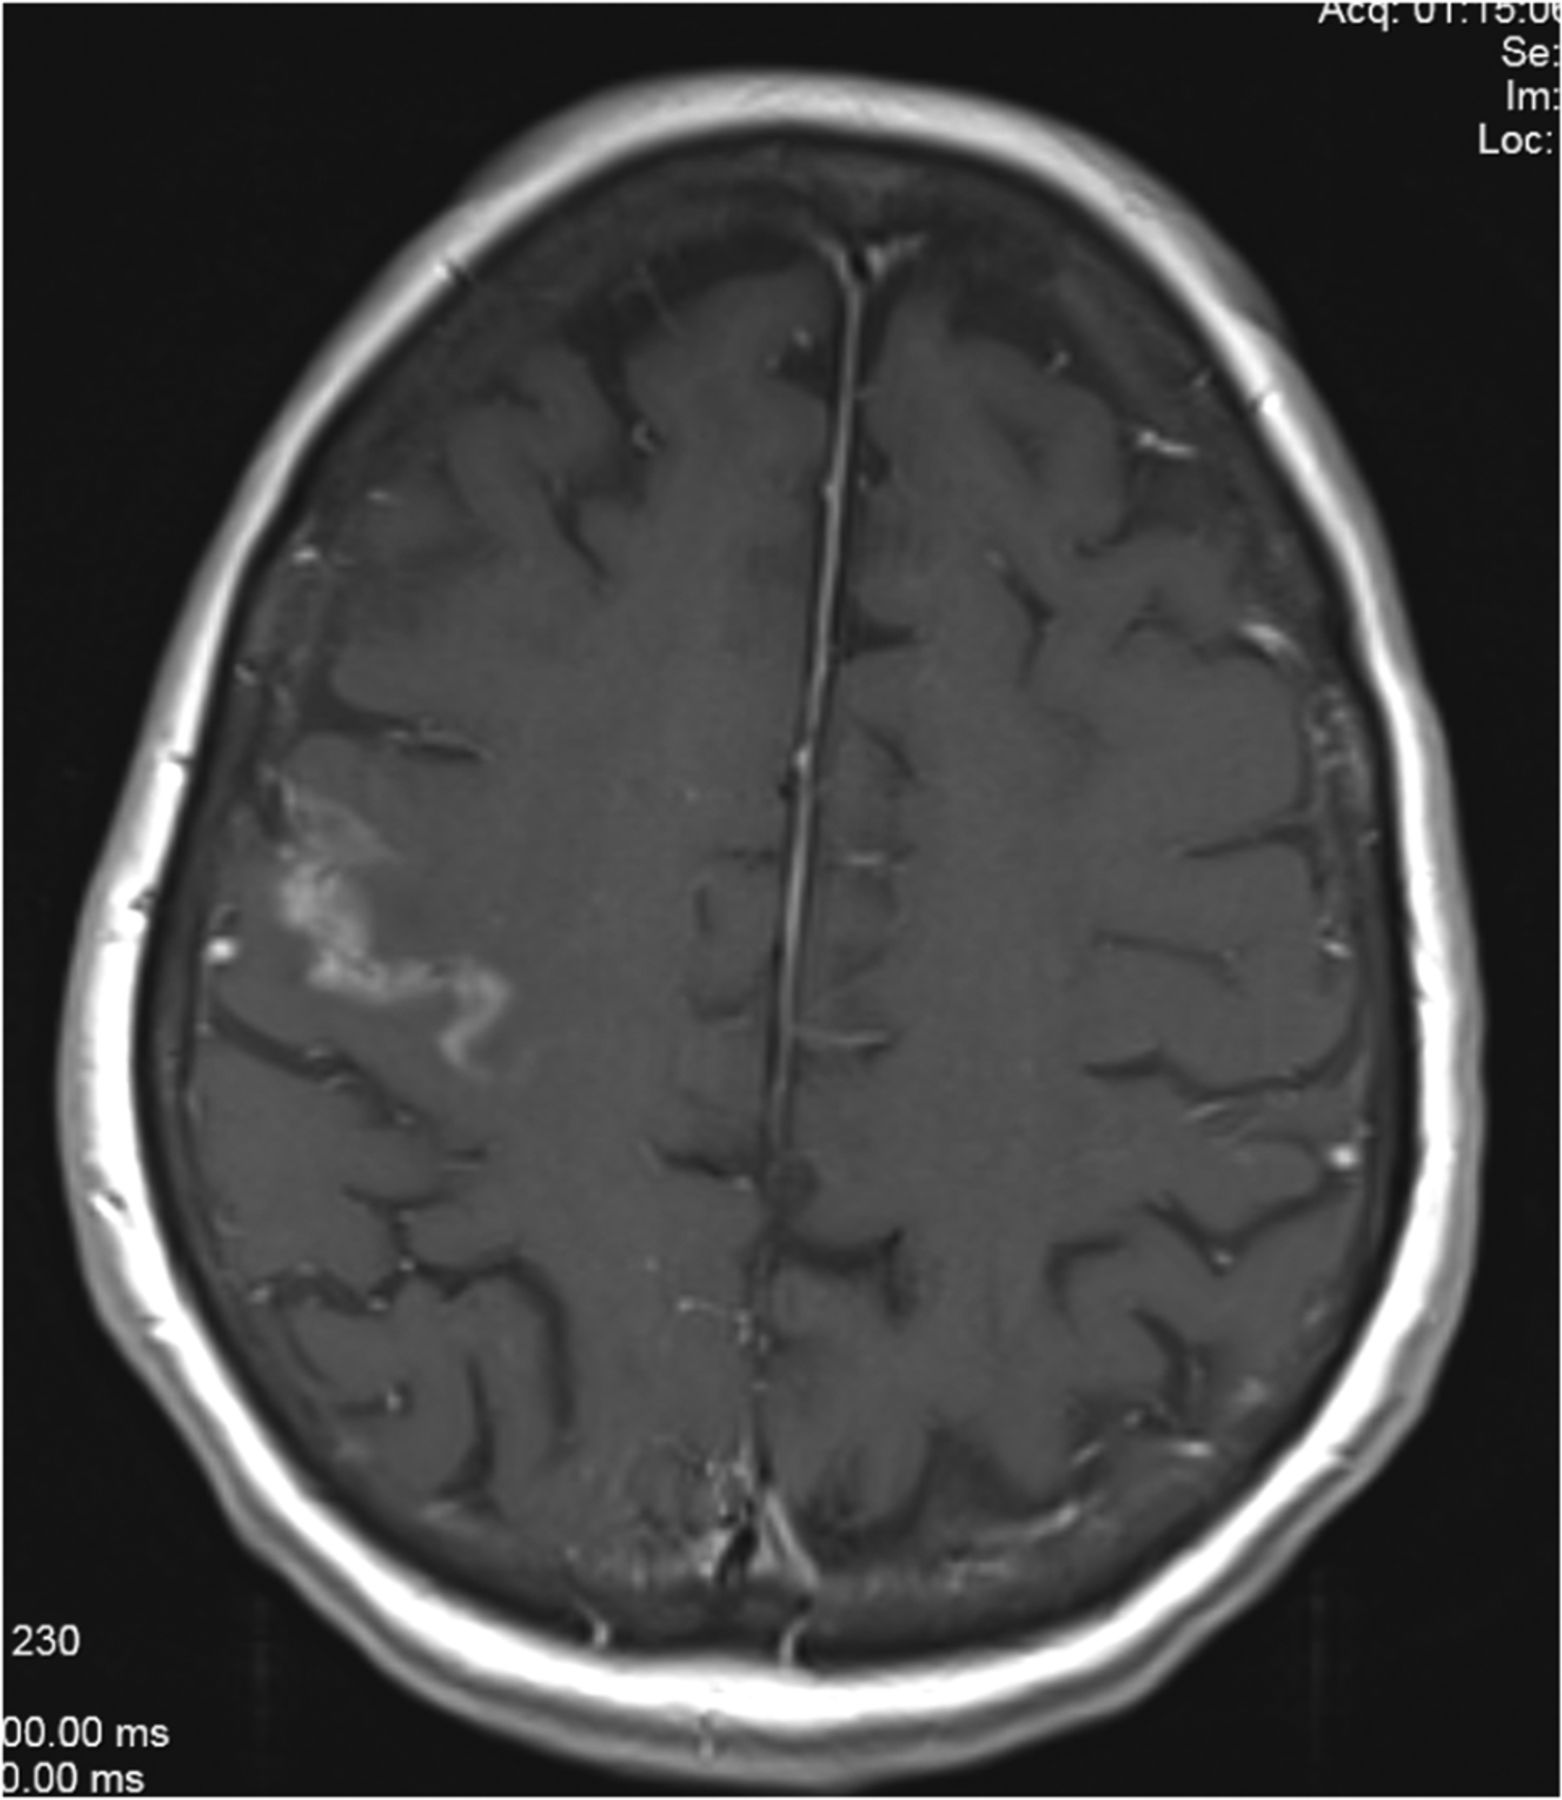

A 77-year-old woman presented with multiple lung nodules, bone metastases, and 2 small brain metastases, one in the cerebellum and the other in the right frontal lobe. A lung biopsy revealed EGFRm NSCLC (L858R mutation), and she was treated with radiation for her primary lung mass and gefitinib. While initially MR imaging revealed a partial response in her brain to gefitinib, 18 months later the lesion in the right frontal lobe progressed with an appearance consistent with FLIP (Fig 5). The patient was asymptomatic and was treated with WBRT. Following that, brain MRIs performed up to 7 months later revealed marked improvement of the FLIP and stable disease elsewhere, and she remained symptom-free. Ultimately, her systemic disease progressed, and she died 8 months following WBRT.

Brain MR imaging for patient 4, a 77-year-old woman with EGFRm NSCLC. Axial projection demonstrates a right frontal lobe lesion following 18 months of gefitinib treatment.